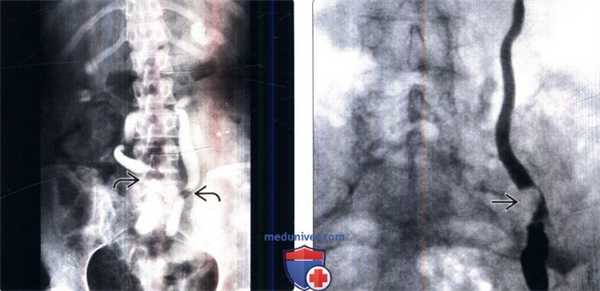

(Слева) На рисунке показана нормальная анатомия мочеточников. Они берут начало от лоханки и продолжаются в мочевой пузырь. Мочеточники лежат на поясничной мышце, проходя кзади от гонадных сосудов. Возле границы входа в малый таз мочеточники проходят над подвздошными сосудами, что может вызвать сдавливание мочеточников извне при визуализации.

(Справа) На экскреторной урограмме определяется небольшая внешняя компрессия и медиальное отклонение мочеточников в месте, где они проходят над подвздошными сосудами. Экскреторная урография повсеместно заменяется на КТ или МР-урографию, которые обеспечивают полноценное исследование почки, мочевыделительных путей и окружающих структур. (Слева) На этой поверхностной 3D реконструкции мочевыделительных путей окно изображения было оптимизировано для отображения собирательной системы почек. Цветовая шкала в данном случае условная, контрастированная моча отображается белым. Менее плотная моча в канальцах пирамид почек и разбавленная в мочевом пузыре отображаются оттенками красного.

(Справа) МРТ в плоскости наибольшей интенсивности, постконтрастное Т1-ВИ (МР-урография), корональный срез: у мужчины 48 лет с анамнезом микрогематурии определяется контрастирование собирательной системы почек, мочеточников и мочевого пузыря. Этот метод является наиболее оптимальным для применения у детей (для исследования врожденных аномалий).